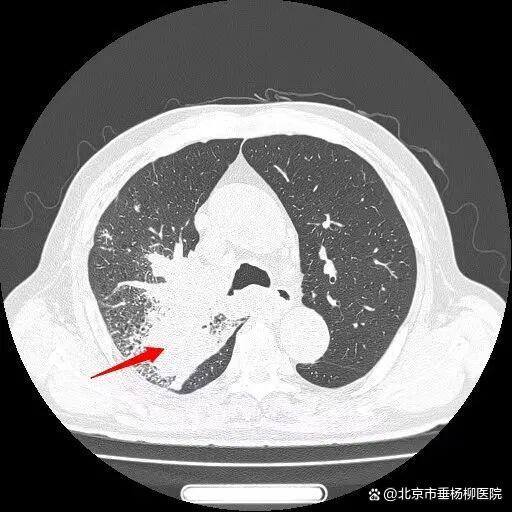

患者王大爷一年前体检发现右肺上叶有一约6×4mm结节,当时未予重视。一年后,他突然出现活动后喘憋症状,复查胸部CT显示右肺上叶后段出现约50×50mm不规则实性团块,影像学高度怀疑肺恶性肿瘤。

入院后,胸外科团队为患者行超声引导下经支气管针吸活检(EBUS-TBNA),病理结果提示为小细胞癌,并发现纵隔淋巴结转移。进一步全身检查显示,患者已出现肋骨及肝内多发转移,诊断为右肺上叶小细胞肺癌(cT3N2M1c IVB期)。

经过一个周期的治疗后,患者喘憋、咳嗽等呼吸道症状明显缓解,复查影像显示右肺上叶肿物显著缩小,疗效评估良好。这一结果让患者及家属重拾治疗信心,也为下一阶段治疗奠定了基础。